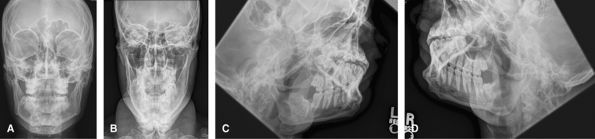

Face

Good initial screening test for facial trauma. If found, these will usually be followed up with CT to show the full extent.

Figure 45 (A) Occipitofrontal. (B) Occipitomental. (C) Occipitomental with 30-degree cranial angulation. (D) Lateral face.

Orbits

Useful to look for any destructive bony lesion about the orbit. Replaced by CT when available.

Figure 46 (A) Lateral face. (B) Occipitofacial. (C) Occipitomental.

Eyes

Only indication would be to look for foreign body within

the eye, usually prior to MRI. By looking up and down, it is possible to

see if the body moves with the eye.

Mandible

The 1st investigation to look for mandible trauma, but

also used to look for disease related to the teeth and their sockets. CT

is a useful adjunct for mandibular trauma. The oblique views show the

labeled side as the inferiorly.

Figure 48 (A) Occipitofacial. (B) AP axial. (C) Left inferosuperior oblique. (D) Right inferosuperior oblique.